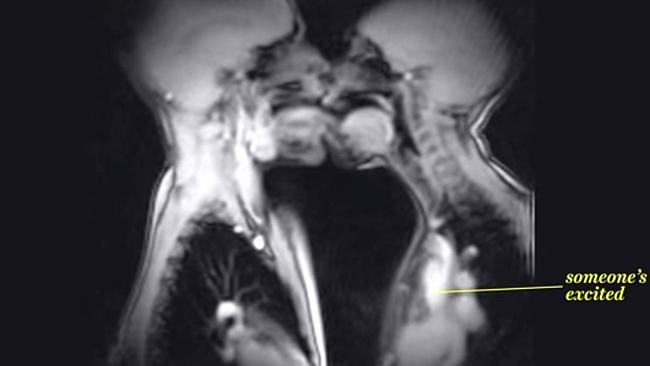

Momente de intimitate intre un barbat si o femeie, surprinse la un RMN. Ce au vrut medicii sa vada. VIDEO

O echipa de medici din Statele Unite au realizat un clip interesant cu ajutorul unor imagini surprinse in timpul unui ...